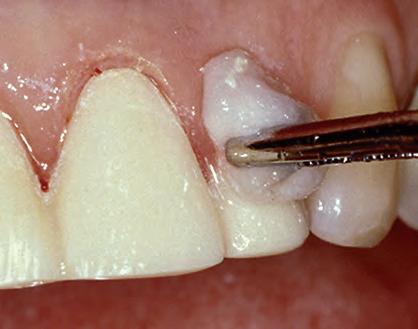

1. Packing Ultrapak cord quickly displaces tissues and improves access for indirect veneer luting.

FOR IMPRESSION TAKING

An astringent is a substance that eliminates permeability of epithelium to tissue fluid flow. The result is a dry field, an important tissue management solution. An ideal impression for successful crowns, veneers, and bridges must accurately capture the preparation margins. This can be ensured only through reliable hemostasis and gingival displacement.

1. Subgingival preparation with bleeding. BLEEDING HEMOSTASIS

2. Scrub Astringedent™ X hemostatic firmly against bleeding tissues with Metal DentoInfusor™ tip.

CLEANING/TESTINGDISPLACEMENT

3. Firm air/water spray removes residual

and tests tissue for quality, profound hemostasis.

Remove

4. Soak Ultrapak™ knitted cord in Astringedent™ X hemostatic, pack, and leave for 5 minutes.